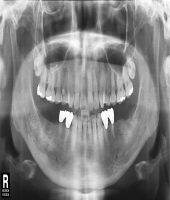

| ● 진료과목 : [심미보철] 돌출치아의 치료

| ● 내용 : 사고로 인한 돌출치아의 치료 |